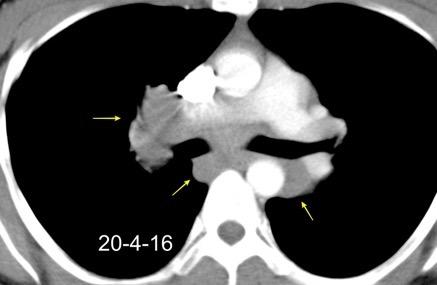

Normal

Espacio normal

Densidad baja uniforme del espacio. Pared interna de BPI-BI visible.

BPI sin alteraciones Ángulo carinal normal

Crecimiento AI

Ganglios Quiste broncogénico

Ganglios subcarinalesl Ángulo carinal normal

Sarcoidosis

Müller NL et al. Subbcarinal Lymph Node Enlargement: Radiographic Findings and CT Correlation. AJR 1985

Criado E et al. Pulmonary sarcoidosis: typical and atypical manifestations at highresolution CT with pathologic correlation. Radiographics. 2010